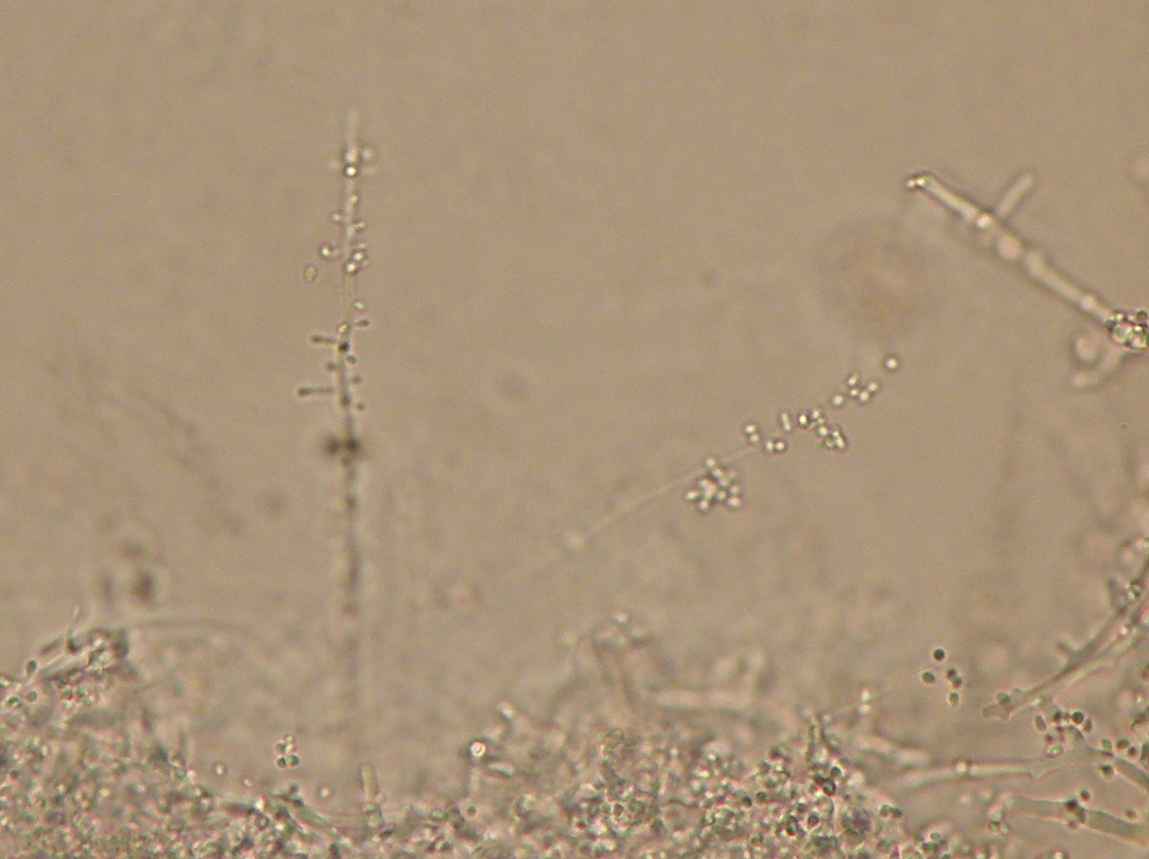

O exame microscópico confirma a identificação de T. mentagrophytes: hifas em espiral, microconideos esféricos.

Hifa em espiral.

Hifa e microconideos.

Hifa com microconideos agrupados.